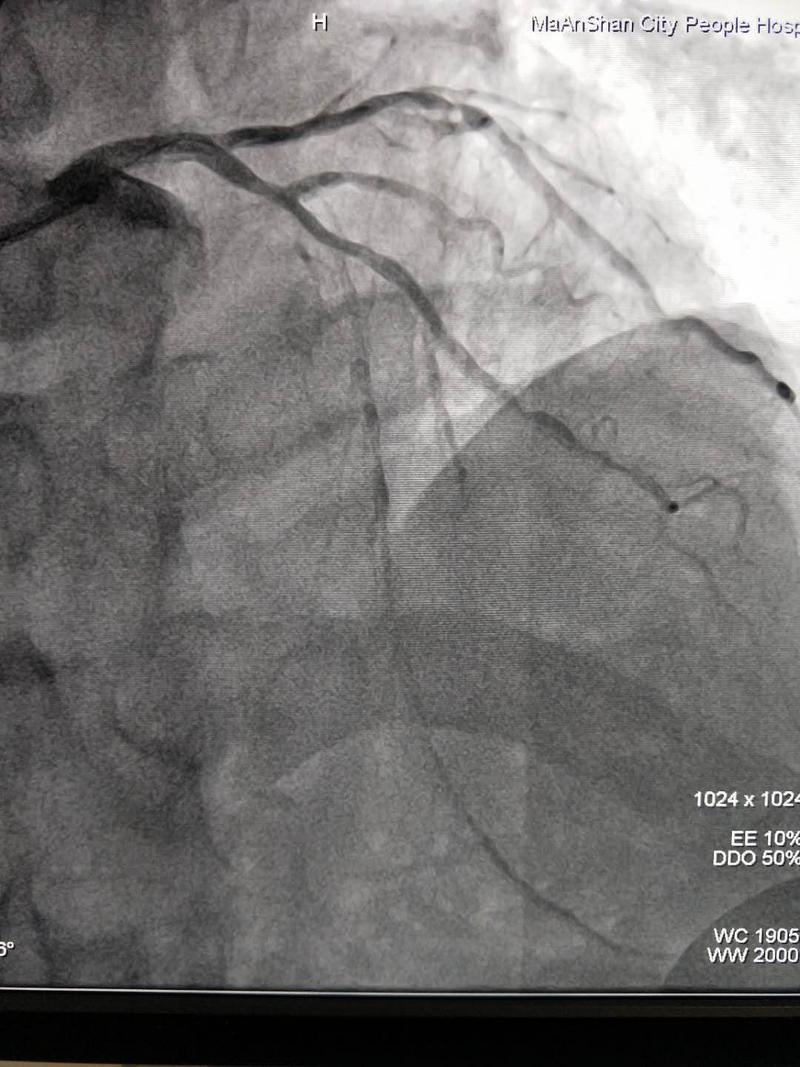

邵旭武副主任仔細(xì)研究了患者的冠脈CTA及冠脈造影結(jié)果,確定了冠脈閉塞長度及閉塞段血管大致走向,制定了詳細(xì)的手術(shù)方案及可能出現(xiàn)的并發(fā)癥的應(yīng)對預(yù)案,帶領(lǐng)夏金發(fā)副主任醫(yī)師、范海主治醫(yī)師等,與技師陶功福、護(hù)士陳俊密切團(tuán)隊(duì)合作,成功攻克左主干CTO。

開通后